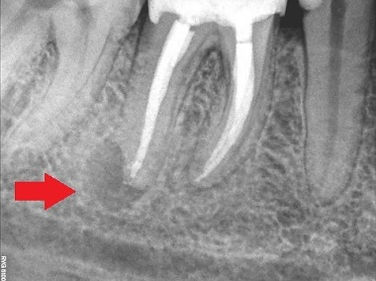

Pacjent lat 44 zgłosił się do gabinetu z obrzękiem okolicy zęba 46( prawa dolna szóstka) po wykonaniu RTG widoczne niedopełnione kanały oraz zmiany okołowierzchołkowe. W tym przypadku ząb został zakwalifikowany do ponownego leczenia kanałowego, polegającego na udrożnieniu, opracowaniu kanałów oraz szczelnym ich wypełnieniu, tylko takie postępowanie daje pomyślne rokowanie co do ustąpienia obrzęku i zmian zapalnych oraz daje szanse zachowania zęba.

Widoczne na RTG zmiany zapalne wokół wierzchołka, niedopełnione kanały

RTG po leczeniu- kanały opracowane i wypełnione do końca